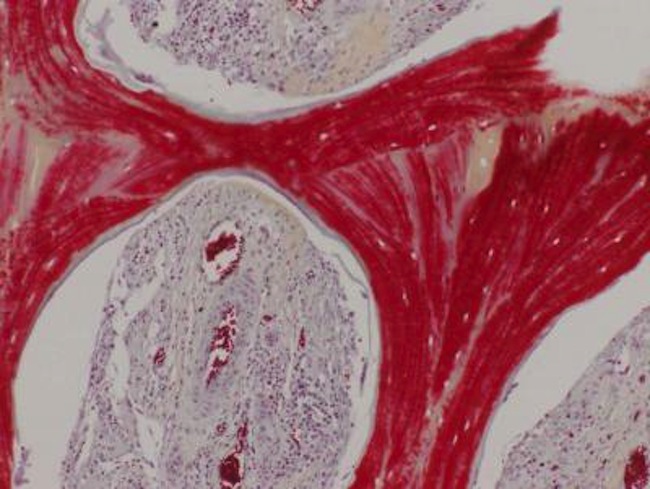

This image shows regenerated bone, with mineralized matrix (red) and strong vascular supply (vessels with red blood cells seen in cavities).

This image shows regenerated bone, with mineralized matrix (red) and strong vascular supply (vessels with red blood cells seen in cavities).